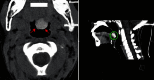

Thyroid ectopy is characterized by the presence of thyroid tissue outside its normal position resulting from a defect of the thyroid diverticulum migration from the base of the tongue until its final pre-tracheal position. One case is presented in a 12-year-old girl patient who consults for a failure to thrive estimated at less than three standard deviations (SD). Bone age was estimated at 8 years late compared to chronological age. The hormonal assessment showed hypothyroidism with negative thyroid antibodies. Cervical ultrasound was revealed thyroid parenchyma pre-dominantly left in place while sweeping the area under chin showed a nodular formation of the base of the tongue. Thyroid scan with technetium 99 m showed a selective uptake of radiotracer in sublingual position. Cervical computed tomography revealed a posterior median sublingual mass spontaneously hyperdense and enhancing sharply after injection of contrast. Treatment with thyroxine allowed obtaining euthyroidism. This case asks us to be careful before aetiological diagnosis of hypothyroidism in children, because although this is rare, the presence of a thyroid parenchyma up to the cervical ultrasound does not eliminate the presence of ectopic tissue.